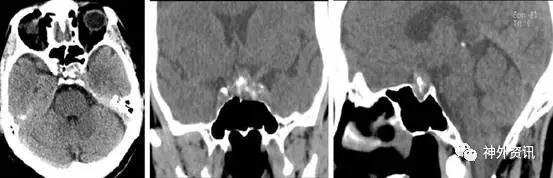

入院后复查头颅CT,示蝶鞍扩大,鞍区见不规则团块状软组织密度影,边界模糊,病灶内见钙化灶,CT值140,鞍底及蝶窦后壁骨质有破坏吸收(图1)。

图1. 头颅CT示鞍区不规则团块状软组织密度影,其中可见结节状钙化灶